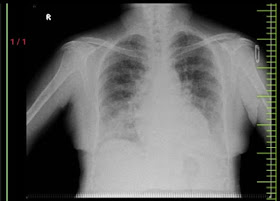

[01-05-2025 16.13] PPM 1: Update chest X-ray

X-Ray Findings (Frontal Chest X-ray):

Cardiothoracic Ratio: Appears mildly increased — suggests possible cardiomegaly.

Lung Fields:

Interstitial markings are mildly prominent bilaterally, more so in lower zones — could indicate pulmonary congestion or early interstitial edema.

No focal consolidation or cavitation seen.

Costophrenic Angles: Poorly visualized, possibly due to patient positioning or early pleural effusion.

Diaphragm: Blunted; again, possibly related to pleural effusion or low albumin status causing ascites pushing the diaphragm.

Bones/Soft Tissues: No acute bony injury; soft tissues seem unremarkable.

[20-05-2025 10:53] PPM 3: This is a chest X-ray (PA view). While a full evaluation ideally includes clinical context, here's a general assessment based on what is visible:

---

General Observations:

1. Image Quality:

PA view confirmed.

Exposure appears adequate—vertebrae are visible behind the heart.

Rotation: Slight rotation may be present (the spinous processes are not exactly midline between clavicles).

Inspiration: Lung fields appear adequately expanded (approx. 6-7 anterior ribs visible).

Findings:

1. Lung Fields:

No obvious consolidation, mass, or pneumothorax.

Bilateral lung fields appear relatively clear.

Mild increased bronchovascular markings could be present, suggestive of interstitial prominence or vascular congestion, but it's subtle.

2. Cardiac Silhouette:

Appears normal in size (cardiothoracic ratio < 50%).

No signs of cardiomegaly.

3. Diaphragm and Costophrenic Angles:

Diaphragmatic contours are sharp.

Costophrenic angles are clear—no blunting suggesting pleural effusion.

4. Mediastinum and Trachea:

Trachea appears central.

No obvious widening of the mediastinum.

5. Bones and Soft Tissues:

No obvious fractures of ribs, clavicles, or spine.

Bilateral round opacities seen in both hemithoraces near mid-lung zones—these are likely nipple shadows, often mistaken for nodules.

Shoulders and upper limbs within normal limits as seen.

Impression:

Essentially normal chest X-ray.

Bilateral rounded opacities are consistent with nipple shadows—a normal variant.

No signs of acute infection, effusion, or pneumothorax.

No cardiomegaly or overt pulmonary pathology.

If you have any clinical background (e.g., symptoms like fever, cough, trauma, or known cardiac issues), I can tailor the interpretation further.